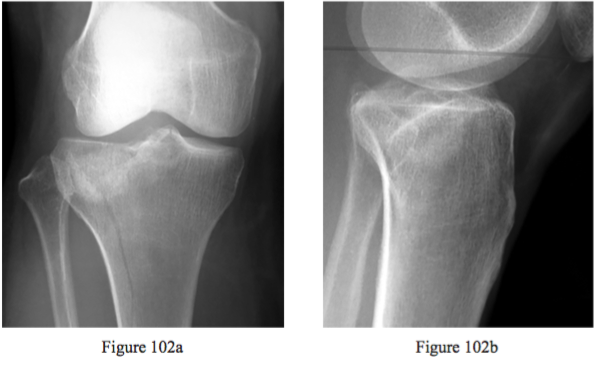

Question 102

Figures 102a and 102b are the radiographs of a 60-year-old woman who slipped and fell and is unable to bear weight. In the emergency department, she was found to be neurologically intact and had good pulses. What is the most likely diagnosis?